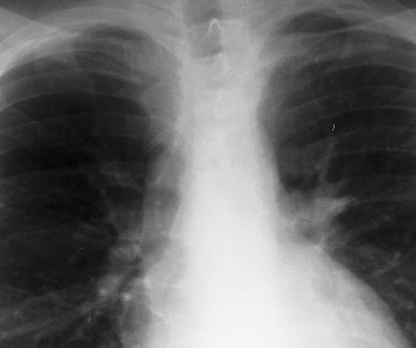

◂Breast Anatomy